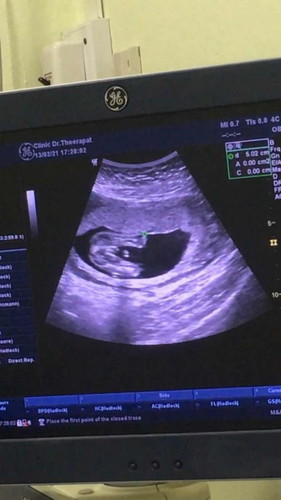

อยากทราบว่าแบบนี้น้องเป็นผู้ชายหรือผู้หญิงค่ะพอดีว่าดูไม่เป็นค่ะ #ขอบคุณสำหรับคำตอบค่ะ

ถ้าถ่ายภาพนี้ให้หมอน่าจะแจ้งเพศให้แล้วนะคะแม่ ถ้าไม่บอกส่วนตัวมองว่าชายค่ะเพราะเห็นจุดขาวๆที่โพล่จากตัวออกมา แต่ถ้าจุดขาวๆนั่นแค่เงาไม่ใช่ก็คือลูกสาวทันทีค่ะ (เดานะคะเราไม่มองเก่งเหมือนหมอ)

ทายว่า ผญ นะคะ คนกลางเราซาวด์มามี 3 ขีดแบบนี้เป็น ผญ ค่ะ หมอที่ซาวด์ให้เราบอกว่า ผญ 100% ออกมา ญ จริงๆเลยค่ะ

น่าจะผญนะคะเห้นเหมือนมีเเคมที่โผล่ออกมาอาจจะเป้นสายสะดือ

น่าจะชายค่ะ เพราะโผล่มาแบบนี้เหมือนกัน ตรวจ 16วีค

น่าจะชายนะคะเหมือนกันเลย

น่าจะผู้หญิงค่ะ

ผู้ชายคร่าจู๋โผล่

น่าจะผู้ชายนะคะ